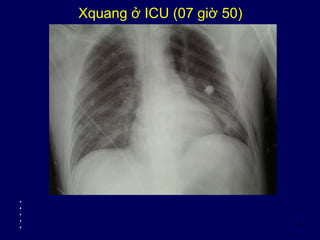

Xquang ở ICU (07 giờ 50)

• NKQ không bị vào sâu một phế quản gốc

• Gẫy xương sườn nhiều tầng

• Vòm hoành trái nhìn quá rõ + góc cùng sườn hoành trái + tràn khí dưới da ngực trái = nghi ngờ

tràn khí màng phổi phía trước bên trái ?

• Khí bên bờ trái cạnh xương ức = tràn khí trung thất trái?

• Không rõ đụng giập phổi phải